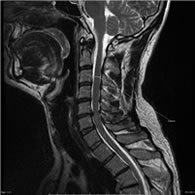

• Resonancia Magnética de la columna vertebral es el principal método de estudio para el canal estrecho cervical. Permite ver la compresión medular y los niveles en los que ocurre; permite evaluar si hay señal de sufrimiento medular y si la compresión es predominantemente anterior o posterior.

El canal estrecho cervical consiste en la reducción del diámetro anteroposterior del canal espinal en la región cervical. Es producto de un proceso degenerativo relacionado con el envejecimiento. Es la causa más frecuente de compromiso medular cervical de origen no traumático en pacientes de más de 60 años.

Por el proceso de envejecimiento de la columna se producen alteraciones espondilóticas. Estas se inician con la degeneración de los discos intervertebrales, lo que genera sobrecarga a nivel de las articulaciones posteriores de las vértebras; con formación de osteofitos (formaciones óseas), hipertrofia de ligamentos y superficies articulares. Estos fenómenos, asociados o no a protrusiones discales, llevan a un estrechamiento del canal espinal, con compresión medular y raquídea; así como alteraciones vasculares.